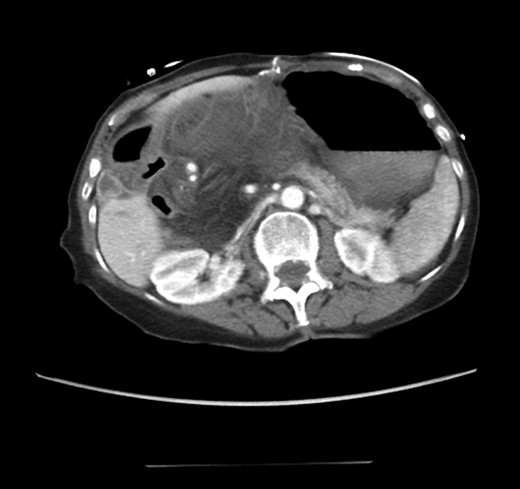

An 81-year-old female with a medical history of CAD with stents, hyperlipidemia, hypothyroidism, GERD, recent UTI, pancreatic cyst, constipation, anemia and leukopenia presented to the ED with a 1 day history of mild, diffuse and cramping abdominal pain. The patient was unable to give an accurate history, but the son at bedside supplemented this reporting that for several years the patient had been experiencing ill-defined abdominal discomfort. Physical exam showed a soft abdomen with mild tenderness and no evidence of peritonitis. A CT scan of the abdomen and pelvis with IV and PO contrast (Fig. 1) showed edematous changes to the mesentery of the small and large bowel with swirling of vessels indicative of internal hernia. The stomach was also noted to be distended with both air and fluid as a consequence of posterior compression by the hernia contents (Fig. 2). A surgical consult was obtained, a nasogastric tube and Foley catheter were placed, antibiotics were started, and the patient was taken for an exploratory laparotomy. Upon entering the abdomen through a vertical midline incision, 1.5 l of ascites was drained revealing a diffusely edematous mesentery. A large portion of the small bowel was seen to be herniated through the Foramen of Winslow (Fig. 3). A Kocher maneuver and division of the gastrocolic ligament were then performed to allow release of the herniated small bowel. It was at this time that, in addition to small bowel, a large portion of the ascending and transverse colon was noted to be herniated through the foramen of Winslow. The small bowel was also seen to be torsed about its own mesentery. Normal anatomy was restored and the bowel noted to be healthy and viable with peristalsis (Fig. 4). Due to the large size of the foramen after reduction and enlargement, it was deemed best to leave it open to prevent any further incarceration or strangulation. The abdomen was closed and the patient tolerated the procedure well. At a follow-up visit 2 months later, the patient had well-healed incisions, was doing well, tolerating a diet, and gaining weight appropriately.

Diagnosing an internal hernia is frequently accomplished using physical exam and CT imaging. Abdominal X-ray does have some nonspecific findings suggestive of internal hernia but is usually inadequate for diagnosis. Diagnosis of a foramen of Winslow hernia, however, is only accomplished in 10% of patients preoperatively [3]. As previously mentioned this diagnosis is rare and often presents with vague obstructive type symptoms. This likely contributes to the low occurrence of accurate preoperative diagnosis. However, several radiographic findings were seen in this patient that suggested a foramen of Winslow hernia preoperatively. First, there is visible swirling of the mesentery on the CT scan that is indicative of internal hernia (Fig. 1). Second, there are loops of small bowel that can be visualized between the IVC and the edge of the liver in a supra renal position along the lesser curvature of the stomach (Figs 1 and 2). When compared to a CT of the abdomen and pelvis obtained 4 years prior to presentation, there is actually evidence that this patient had a non-obstructing foramen of Winslow hernia at that time as demonstrated by bowel being visualized in the lesser sack (Fig. 5). These findings, especially small bowel along the lesser curvature of the stomach, are inconsistent with normal anatomy and strongly indicative a foramen of Winslow hernia.